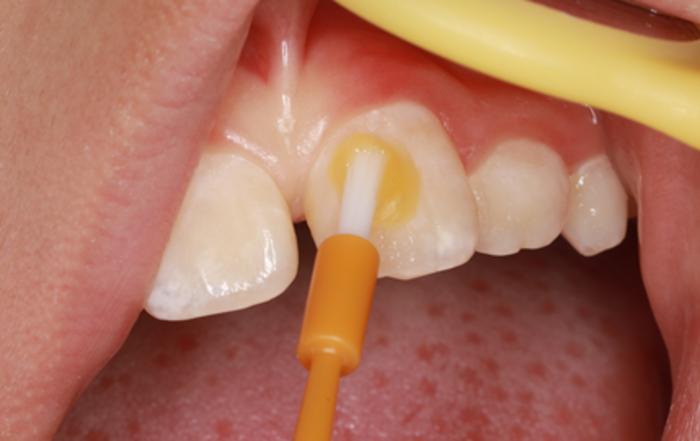

涂氟,就是将氟化物直接涂于牙齿表面 。

形象地说,涂氟就像是给牙齿穿上一件有力的防龋衣,在短时间内, 为牙齿局部提供较高浓度的氟,增强牙齿的抗龋能力。

如图所示,正在给孩子“涂”氟